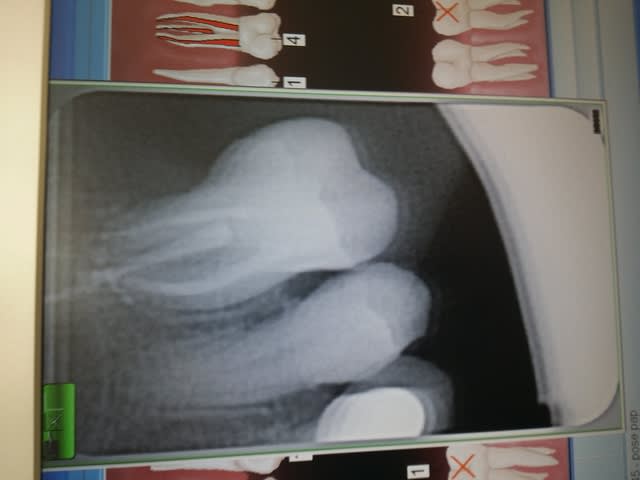

Je fais appel à vos idées ;je me trouve face à une 36 que je viens de dévitalisée car trés délabrée et cette dent présente une racine unique avec une chambre pulpaire super large ,je vais essayer de vous mettre la radio ;

probléme je ne pense pas que mes forets de chez APOL soit en diametre suffisant pour trouver un contcat sur les parois dentinaires et je n'aimerais pas que mon ancrage soit scéllé dans de la gutta seulement